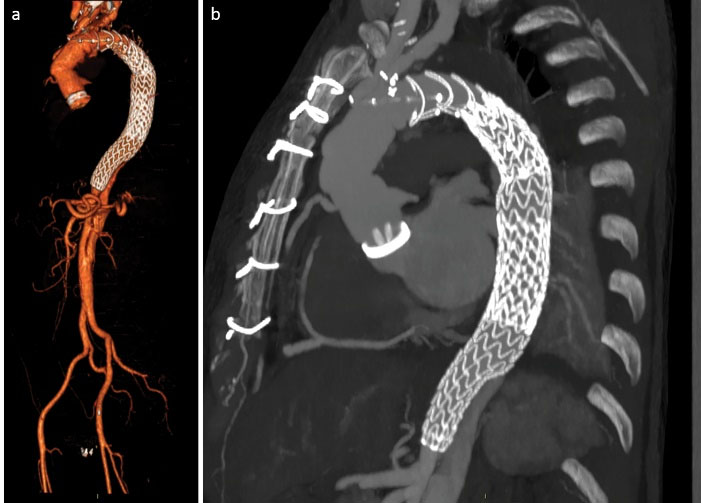

A 56-year-old male, previously operated with mechanical Bentall procedure and right coronary artery bypass grafting for acute type A aortic dissection, was admitted to our hospital with the diagnosis of residual type A chronic aortic dissection to undergo FET procedure. Total arch replacement with FET was performed in operative room (OR) using a 28/30 mm Thoraflex hybrid prosthesis (Vascutek, Inchinnan, UK). Briefly, after circulatory arrest and cerebral protection with selective bilateral antegrade cerebral perfusion at a target nasopharyngeal temperature of 25 °C, the hybrid prosthesis was deployed into the descending thoracic aorta. Distal anastomosis was performed at Ishimaru zone 2 of the aortic arch. Systemic perfusion was re-established through one of the side-branch of the hybrid prosthesis and then, the supra-aortic vessels re-implantation and the proximal anastomosis were completed. The post-operative period was uneventful although the pre-discharged computed tomography angiography (CT) scan control showed the incorrect deployment of the distal endovascular portion of the Thoraflex in the false lumen (). The residual flap length was about 25cm, extending from the middle tract of thoracic aorta to the sub-renal tract; celiac trunk, superior mesenteric artery and right renal artery originated from true lumen, left renal artery from false lumen. Then, the aortic team decided to perform an angiography to evaluate the feasibility to access the false lumen through an intimal tear visualized in the pre-discharged CT examination in the middle portion of the thoracic aorta (), in order to evaluate the possibility to create a communication between the stent graft portion of the Thoraflex in the false lumen and the true lumen. After the angiographic confirmation of the feasibility of the procedure, the patient was then scheduled to perform a thoracic endovascular aortic repair (TEVAR). In a hybrid operative room, with the support of intraoperative transesophageal echo-guidance, the access to the false lumen was through the cannulation of the intimal tear located in the middle tract of the thoracic aorta. Then, the cannulated tear was dilated with the use of balloon catheter (Medtronic Evercross Pta Baloon Catheter, 6x60mm and 8x60mm, Minneapolis, MN) (). After positioning of an ultra-stiff guide wire through the dilated tear, two stent grafts were released proximally (Gore Tag Thoracic Stent Graft 28 mm x 28 mm x 150 mm, Usa AZ) in the portion of the Thoraflex deployed into the false lumen and distally (Gore Tag Thoracic Stent Graft 31 mm x 31 mm x 150 mm, Usa AZ) in the true lumen of thoracic aorta above the celiac trunk (). The intraoperative angiography showed the successful outcome of the procedure (); the postoperative period was uneventful and the patient was discharged in seventh post-procedural day. The pre-discharged CT scan control confirmed the complete exclusion and thrombosis of the false lumen in the thoracic aorta (). The CT scan performed at two years follow-up confirmed the good result of the procedure ().

jcvtr-14-205-g002

Figure 2. Intraoperative cannulation and dilation of the thoracic intimal tear (a) and angioscopy control after deployment of the stent graft (b).

jcvtr-14-205-g003

Figure 3. CT scan control at discharge (a) and 2 years follow-up (b) showing complete exclusion and thrombosis of the thoracic false lumen.